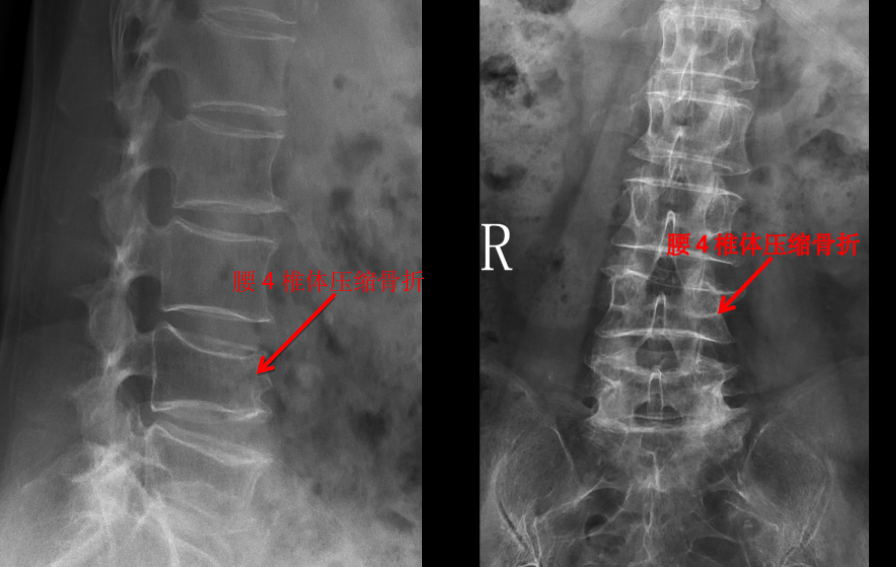

我們管 X 線(xiàn)檢查叫 X 光片、照相或拍片。在 X 光片里,我們能看到脊柱有沒(méi)有骨折,有沒(méi)有骨質(zhì)破壞,有沒(méi)有脊柱側(cè)彎、有沒(méi)有骨質(zhì)增生等。一些有經(jīng)驗(yàn)的大夫,可以通過(guò)椎間隙高度的丟失判斷椎間盤(pán)的退變程度。

但是對(duì)于大部分軟組織病變?nèi)缱甸g盤(pán)、椎管內(nèi)神經(jīng)、有沒(méi)有占位性病變等卻無(wú)能為力。如果患者有壓縮骨折,X 光片也無(wú)法判斷是新鮮骨折還是陳舊骨折,這樣也就無(wú)法定制下一步診療計(jì)劃。

前面提到的腰椎壓縮骨折,X 光片可以看出楔形變,但無(wú)法判斷新鮮骨折還是陳舊骨折,進(jìn)一步完善腰椎 MRI 才能明確診斷,做出下一步治療計(jì)劃。